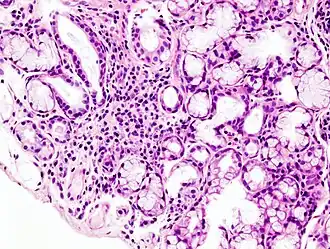

Image histopathologique d'une infiltration lymphoïde focalisée de la glande salivaire accessoire, associée au syndrome de Gougerot-Sjögren. Biopsie de la lèvre. Coloration à l'hématoxyline et à l'éosine.

S'il n'existe pas d'anticorps anti-SSA ou anti-SSB dans le sérum, le diagnostic de certitude est apporté par l'analyse anatomo-pathologique d'une biopsie des glandes salivaires accessoires.